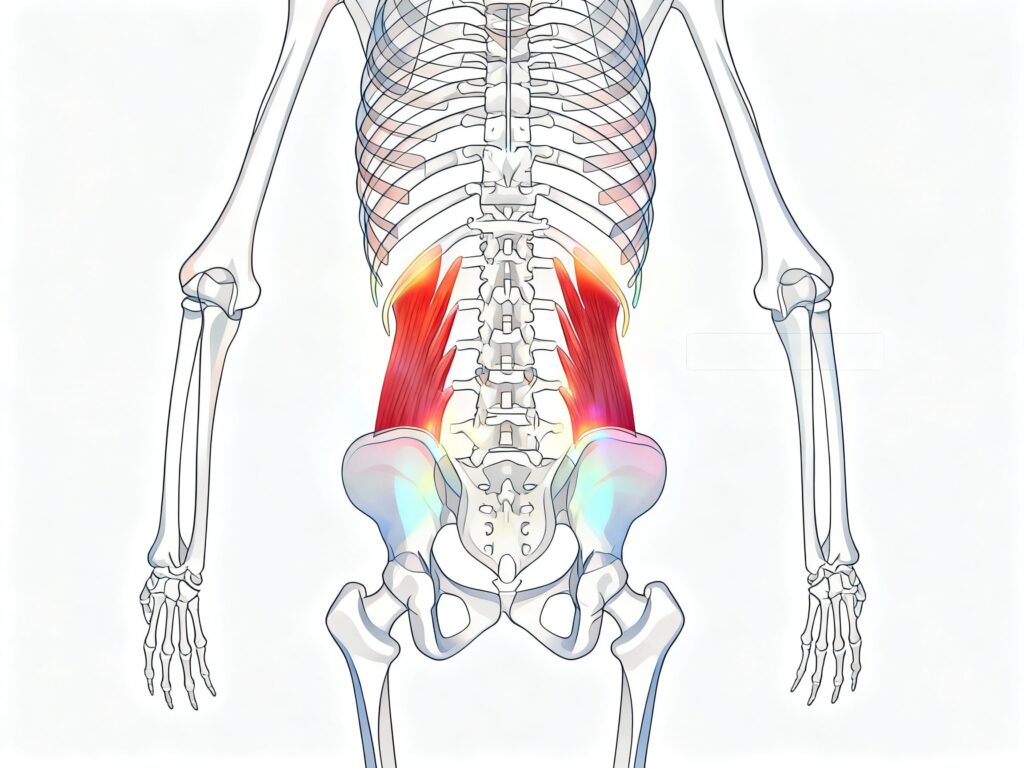

Dor Miofascial no Quadrado Lombar – Causa comum de dor na coluna lombar

Quadrado Lombar: O Vilão Secreto da Dor nas Costas Se você tem uma dor nas costas “baixa” que nunca passa, que piora ao levantar da cama ou sair do carro, e que às vezes parece descer para o quadril, você pode estar tratando a coluna errada. O culpado muitas vezes não é a hérnia de […]